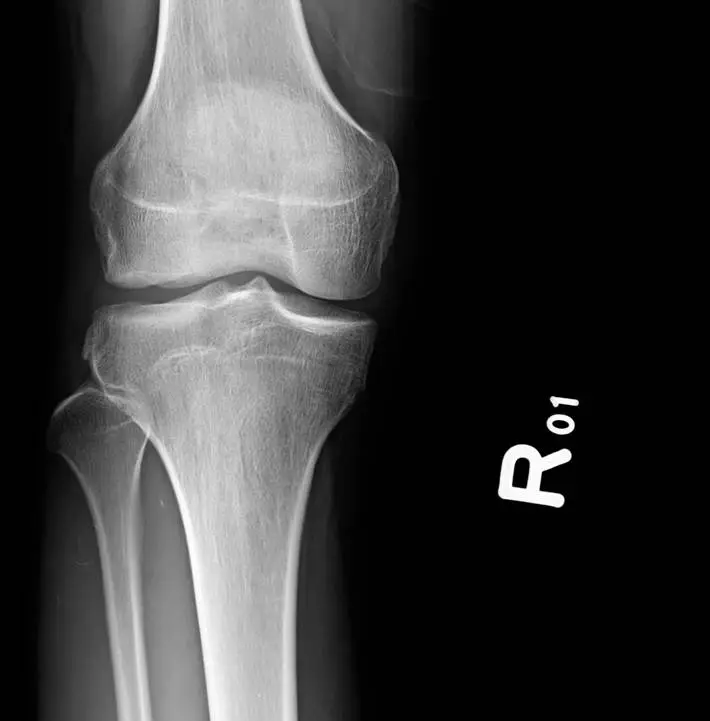

X 光片(前後位)

外側脛骨平台可見一彎曲的細小骨片平行於平台緣,符合 Segond fracture(lateral capsular sign)的典型表現 (radiopaedia.org)。 -